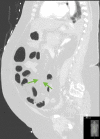

The prothrombotic nature of severe acute respiratory syndrome coronavirus 2 (SARS-CoV-2) has been well-established since the start of the global coronavirus disease 2019 (COVID-19) pandemic. Mesenteric artery thrombosis and acute mesenteric ischemia are, on their own, rare occurrences and often present with fatal gastrointestinal (GI) pathologies requiring quick identification and intervention by the clinician to improve clinical outcomes. SARS-CoV-2 infection can present with acute GI pathologies and warrants further investigation regarding anticoagulation therapy in COVID-19 positive patients. We report on a 64-year-old woman infected with SARS-CoV-2 who presented with superior mesenteric artery thrombosis and acute intestinal ischemia.